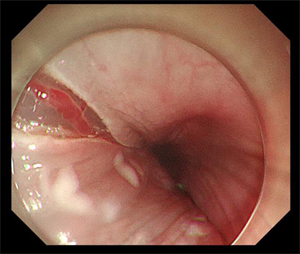

5月14日,80岁的李大爷(化名)因“再发胸闷气喘加重10天”在我院心内科住院期间,经检查,胃镜显示该患者为食管距门齿25~35cm可见两处1.5*2.0cm发红不规则糜烂,病理活检显示为鳞状上皮呈高级别上皮内瘤变(高级别上皮内瘤变相当于原位癌,也称之为食管早癌)。由于该患者曾多次因”慢阻肺、心脏瓣膜病、心功能不全、慢性房颤”住院治疗,且已有80岁高龄,若进行食管癌手术切除治疗风险大、预后生活质量会明显下降。消化内科吴斌及团队根据老人的实际情况反复研究,决定为李大爷行食管早癌消化内镜下黏膜剥离术。

是通过内镜前端针对粘膜、病灶周围进行注射,在胃镜下对病变粘膜进行切割剥离,通过剥离使病灶离开胃壁或者是粘膜层。ESD术具有创伤小、不改变消化道结构、避免外科手术风险、提高术后生活质量等优点,可以帮助早期肿瘤病人达到治愈的目的。